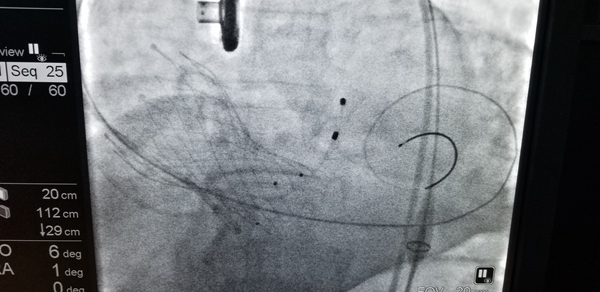

74岁的陶某是一名重度主动脉瓣狭窄的患者,曾多次因心绞痛及心力衰竭住院,生活质量极差,并且症状逐渐加重,传统药物治疗无法明显改善患者的病情。经胸心外科医生会诊后建议开胸行主动脉瓣置换术。但开胸手术痛苦大,风险高,术后并发症多,这让病人及家属十分担忧。此后陶某听闻我院心内科严金川主任对心脏的介入治疗有着丰富的经验以及高超的技术,于是前来就医询问是否可以通过微创介入手术换瓣。严主任仔细询问患者病史并做了详细的相关检查,确定该患者符合经导管主动脉置换术(TAVI)的适应症,并且无微创介入手术禁忌症。医院领导高度重视该项新技术的开展,多次组织心血管内科、心外科、麻醉科、影像科、心脏超声、医务及护理等多学科多部门反复讨论,最后经医学伦理委员会专家投票一致通过了该项新技术的临床实施。手术方案决定采用经股动脉微创介入方式。由于手术操作复杂,需要多专科团队人员的协作,技术难度高,严主任领衔的心脏介入团队为此进行了缜密准备,制定了详细的风险应急预案,多学科密切配合,最大程度地保障患者的安全。TAVI术中通过股动脉送入介入导管,首先采用扩张球囊对患者重度钙化狭窄的主动脉瓣膜进行预扩张,后将人工主动脉瓣膜送到拟释放位置,经反复造影精确定位,瓣膜位置合适,人工瓣膜顺利释放,替换了原来重度钙化、狭窄的瓣膜,术中经食道超声确认新的瓣膜位置准确、开放自如,无瓣膜返流,患者主动脉瓣的功能得以恢复,手术成功。术后1个小时,患者就已经清醒,目前生命体征平稳,恢复良好,胸闷气喘症状显著改善,现在已可以自由下床活动。